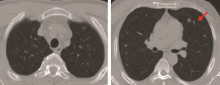

患者男性、51岁, 因“ 涕血3个月” 入院。2010年8月胸部CT检查诊断双肺转移瘤(图1)。2010-09-10我院鼻咽部CT检查示:鼻咽肿物侵犯咽旁间隙、颅底、蝶窦, 伴右颈淋巴结转移(图2); 鼻咽镜行鼻咽肿物活检病理示:鼻咽低分化鳞状细胞癌。诊断为鼻咽低分化鳞状细胞癌cT3N1M1(双肺) Ⅳ c期(AJCC 2010), PS=1。2010-09-21至2011-01-12予TPF方案化疗6周期, 其中紫杉醇256 mg d1、DDP 30 mg d1~d5、5FU 950 mg d1~d5。2周期后(2010-11-04)复查胸部和鼻咽CT示:鼻咽肿物明显缩小, 左上肺前段小结节, 性质待定(图3)。鼻咽部病灶部分缓解(partial remission, PR), 肺部病灶PR, 总评价PR; 4周期后(2010-12-20)复查胸部CT示, 左肺上叶前段纤维灶; 右肺下叶炎性改变, 左肺上叶轻度肺气肿, 肺大泡形成(图4)。4周期后鼻咽病灶PR, 肺部病灶完全缓解(complete remission, CR), 总评价:PR; 6周期后(2011-02-24)复查胸部CT示:双肺多发小结节, 考虑转移瘤可能性大; 肺气肿, 左肺上叶肺大泡形成。鼻咽病灶较前进一步缩小(图5)。6周期后鼻咽病灶PR, 肺部病灶进展(progressive disease, PD), 总评价:PD。

张奕(放射科医师):基于患者的病史和外院CT片, 结合该患者2月份到4月份治疗后复查的情况, 因为该患者肺部的转移瘤在缩小中, 4月份的片中瘤灶基本上消失了, 左上肺有一些囊泡状的空泡影, 考虑为肺气肿(图6)。肺内血行转移小结节有以下三方面的特点:①膨胀性生长, 形态比较饱满, ②多呈类圆形, 边缘比较光滑, ③较少侵犯胸膜。根据以上的特点, 我重新回顾了患者2011年2月的CT片, 逐个小结节分析后认为:左下肺的结节是贴着胸膜塌陷式生长的, 形态不太饱满, 边界也不太光滑。右中肺的几个结节的毛刺非常发达(图7), 意识到以前的诊断有些不对。从图中我们可以清晰地看到, 结节不是特别圆, 边缘不光滑, 形态不饱满, 有塌陷, 有些有毛刺。那么这些小结节是否为转移灶?从影像学上来说, 有以下几点支持转移:①多发小结节, ②肿瘤病史; 以下几点不支持转移:①多处病灶位于胸膜处, 并有牵拉征象, ②多处病灶可见长毛刺, ③多处病灶可见塌陷, 形态欠饱满。至此我们认为, 2月份新发病灶的影像诊断应该是炎性肉芽肿。我们的诊断前后不同, 说明我们对病史的了解和图像的观察不够深入。图8是比较典型的炎性肉芽肿(A、B)和转移瘤病灶(C、D)的CT图像。